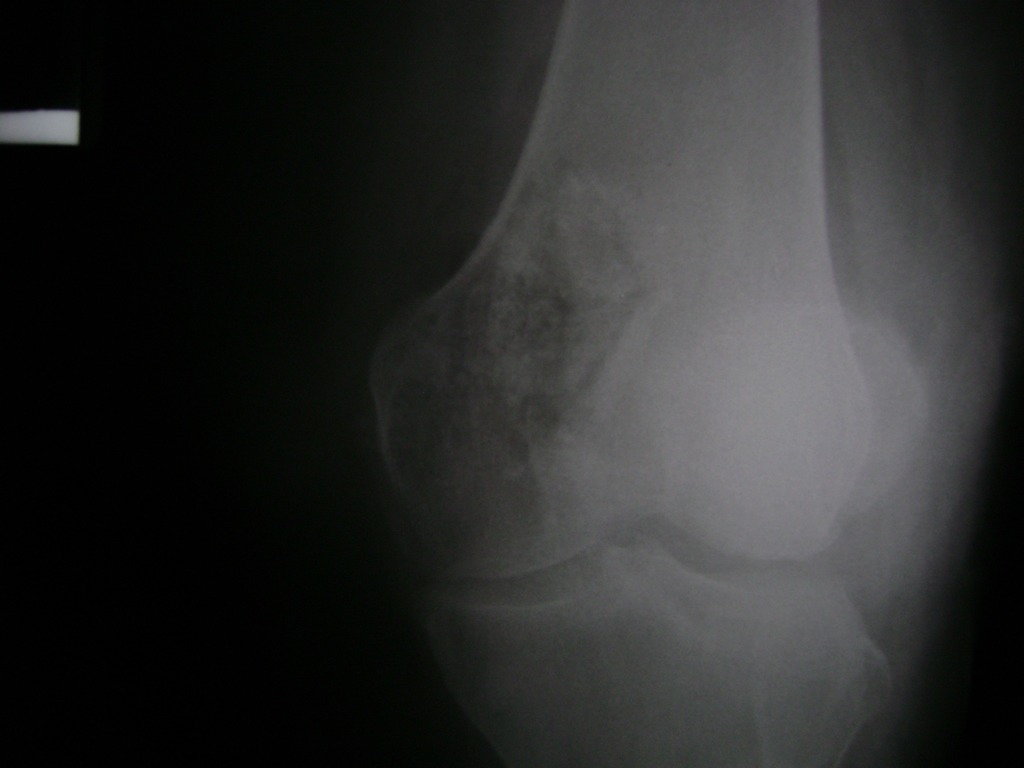

Cirugías de Calcaneo - Rodilla

La artroscopia de rodilla es un cirugía en el cual la estructura interna de la articulación es examinada ya sea para realizar un diagnostico o para realizar un tratamiento, este procedimiento se realiza utilizando un instrumento parecido a un pequeño tubo llamado artroscopio.